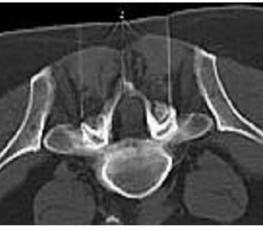

Bei der periduralen oder sakralen Blockade oder landläufig auch Rückenmarksnarkose genannten Infiltration und Überflutung des Nervenwurzelschlauchs (Kaudalsack) im Bereich der unteren Lendenwirbelsäule wird über einen kleinen Zugang im Kreuzbein (Hiatus sakralis) eine Kanüle oder ein Katheter in die Nähe des Nervenwurzelsacks vorgeschoben und dann ein Narkosemittel mit ggf. Beimengungen von Cortison oder einem Enzym appliziert.

Darunter soll es zu einer Blockierung der unteren Lenden- und Sakralnervenwurzeln, welche z. B. durch einen Bandscheibenvorfall oder durch eine Wirbelkanaleinengung gereizt sind, kommen. Die Schmerzen sollen reduziert werden und zudem eine Abschwellung der gereizten Nervenwurzeln erfolgen. Erfahrungsgemäß beträgt die Erfolgsquote 60-70%. Es werden 6-12 Injektionen in unterschiedlichen Zeiträumen erforderlich sein.